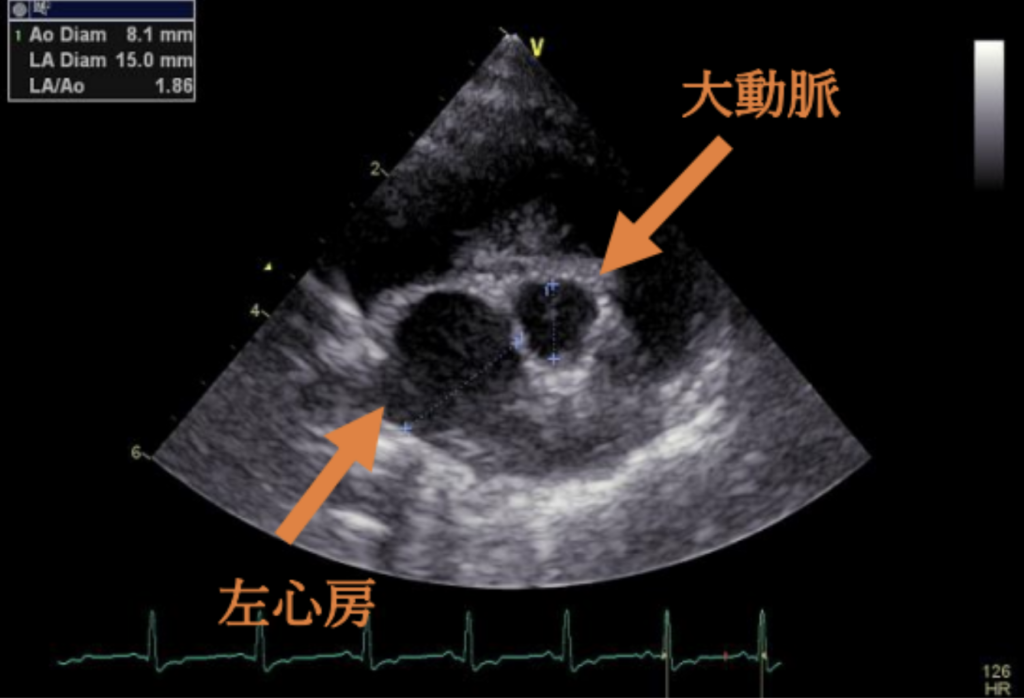

わんちゃんの⼼臓は、右⼼房/右⼼室・左⼼房/左⼼室という4つの部屋からできていま

す。それぞれの間には⾎液が逆流しないように「弁」があります。そのうち、左⼼房と

左⼼室を隔てているのが「僧帽弁」です。

粘液腫様僧帽弁疾患とは、この僧帽弁がしっかり閉まらなくなり、⾎液が逆流してしま

う病気です。初期には症状が出ないこともありますが、進⾏すると⼼臓が⼤きくなり、